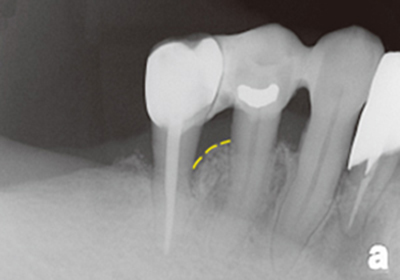

案例1

補骨前

補骨後